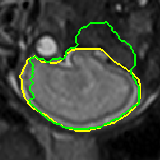

Data augmentation has been widely used for training deep learning systems for medical image segmentation and plays an important role in obtaining robust and transformation-invariant predictions. However, it has seldom been used at test time for segmentation and not been formulated in a consistent mathematical framework. In this paper, we first propose a theoretical formulation of test-time augmentation for deep learning in image recognition, where the prediction is obtained through estimating its expectation by Monte Carlo simulation with prior distributions of parameters in an image acquisition model that involves image transformations and noise. We then propose a novel uncertainty estimation method based on the formulated test-time augmentation. Experiments with segmentation of fetal brains and brain tumors from 2D and 3D Magnetic Resonance Images (MRI) showed that 1) our test-time augmentation outperforms a single-prediction baseline and dropout-based multiple predictions, and 2) it provides a better uncertainty estimation than calculating the model-based uncertainty alone and helps to reduce overconfident incorrect predictions.